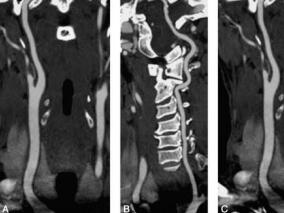

1小时条评论1 病例简介 患者男,68岁,因突发右侧肢体活动不灵伴言语不清2小时于2008年12月7日收入我院神经内科。起病前2小时有反复扛重物史。既往无高血压、糖尿病及冠状动脉粥样硬化性心脏病史。查体:血压120/80mmHg,颈总动脉、椎动脉、锁骨下动脉听诊区未闻及杂音。右侧中...